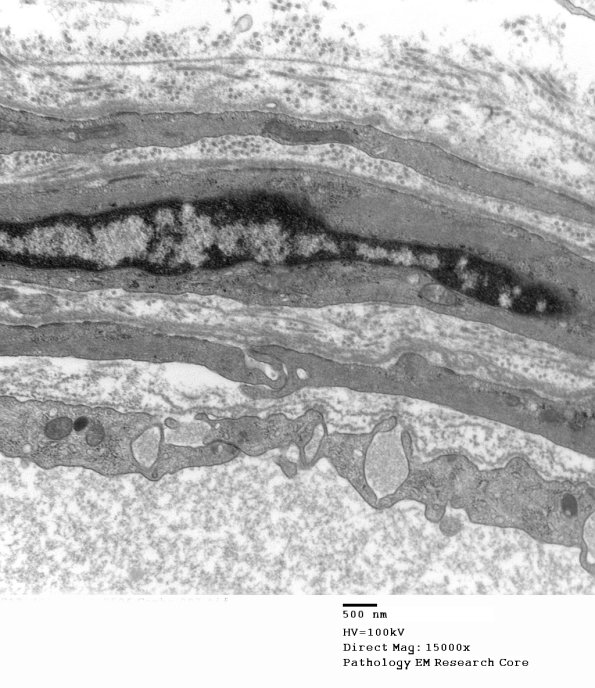

5A1-3 The perineurium as seen at multiple magnifications. The cell to cell junction is well seen in the last image.